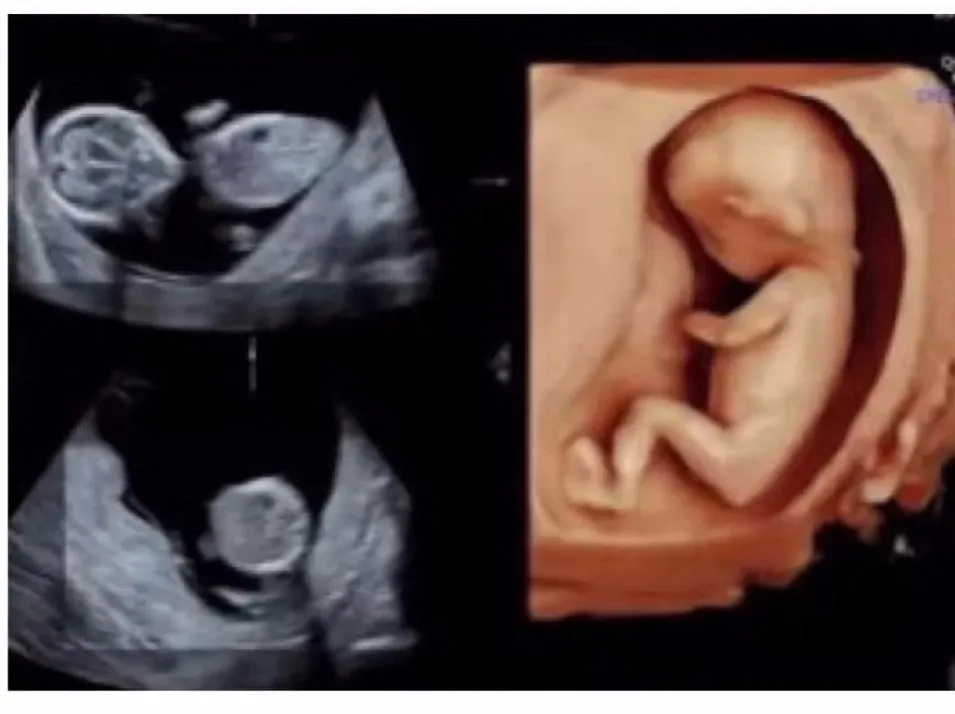

终于,到了李女士万分期待的那一刻,二宝宝就要降生了。在吃完晚饭没多长时间,下午6点钟,李女士感受下面突然一股水流,她觉得不太妙,赶紧联系美琳达客服工作人员,到医院后,经过美琳达住院部医生宋文红和王萍的检查,“李女士是胎膜早破现象,经过系列检查,李女士虽然是瘢痕子宫,但是孩子胎位以及她自身的生产条件是可以试产”。

这个时候,原本计划选择剖宫产的李女士犹豫了,宋文红医生和王萍医生看出李女士犹豫继续劝解“这次检查没有你在生大宝时候出现的羊水少等现象,孩子体重预估是3200克,胎头衔接也很好,作为医生是非常鼓励你试产”,听完之后让李女士有了顺产的信心,与家人商量过后决定选择试产,头一回试产,李女士稍有些紧张,也有很多的疑问,一直在监护她产程情况的宋文红医生和王萍医生都一一耐心地为她解答。而这次的小主人公二宝也是相当努力配合妈妈顺产的决定,晚上9点45分,李女士宫缩频率每2分钟一次,随即李女士被送往产房。

1. 孕期产检实现分区诊疗:更为私密的就诊环境,在每一个独立诊区,都配备有护士站、预诊区、抽血区、心电图、胎心监护、B超,一站式解决每次产检全部的辅助检查。

2. 领先医疗设备、高端配置:提供1台B超为2间产科诊室服务的高配设施,避免妇产科超声检查的长时间拥堵、等待。